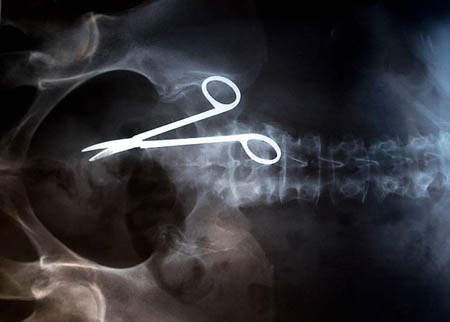

因為手術,而被留在患者體內的剪刀

圖片來自:http://www.po-kaki-to.com/